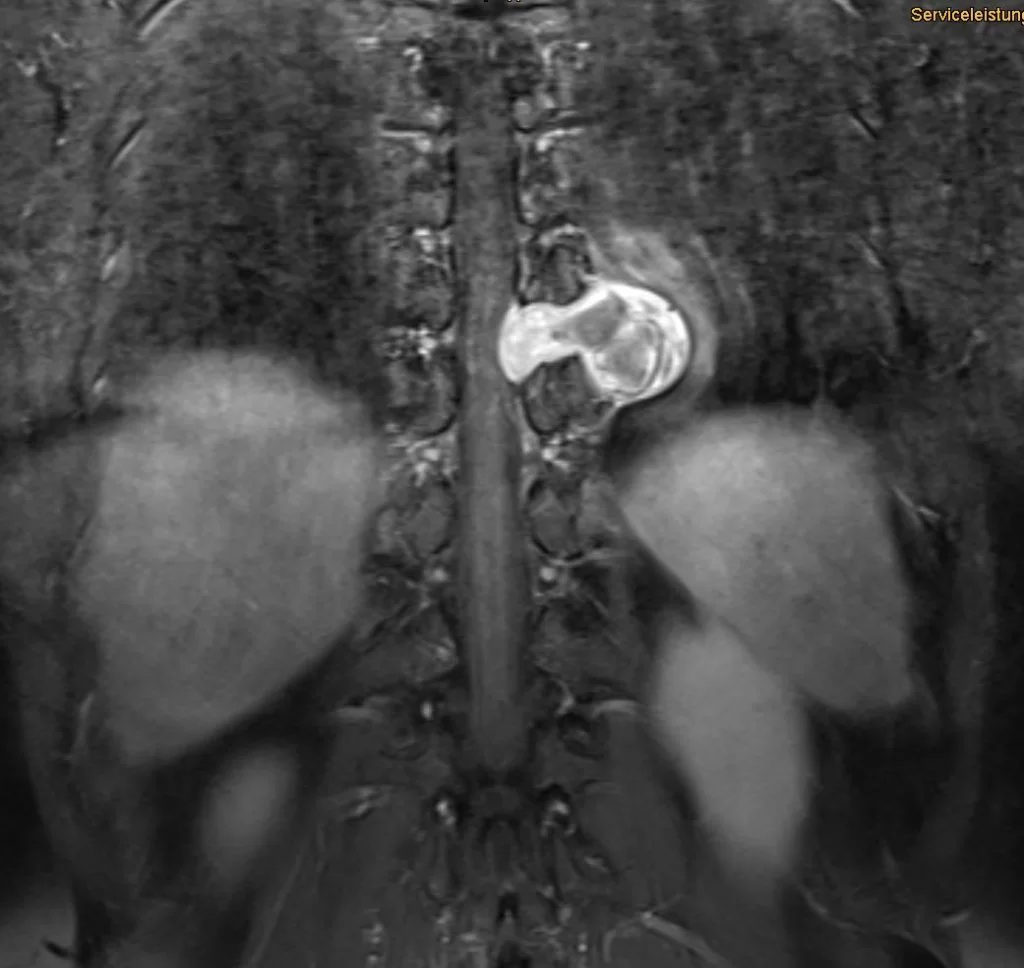

Όγκος Ιερού Οστού (Σβάννωμα)

Ασθενής 55 ετών με γνωστή εκτεταμένη εξεργασία (όγκος) του ιερού οστού. Είχε προηγηθεί προσπάθεια αφαίρεσης της βλάβης. Κλινικά η ασθενής παρουσίαζε προοδευτική επιδείνωση της κλινικής